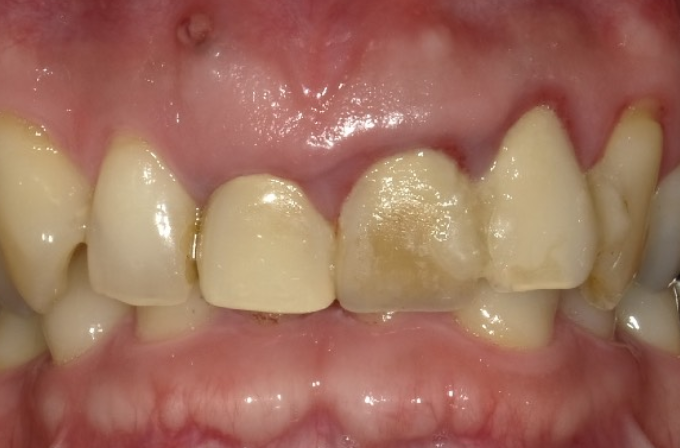

症例3

| 項目 | 詳細 |

|---|---|

| 患者様データ | 40代 男性 |

| 来院時の主訴 | 「前歯を歯磨きすると痛いし、出血する。」 |

| 医院の診断 | 右上中切歯根尖性歯周炎、歯周病 |

| 通院期間 |

6か月 |

| 来院回数 | 10回 |

| 治療費 | 総額:歯周病治療に関しては保険適用診療。その他:370,000円(税抜) 【内訳】 歯周病治療(歯周病検査・歯磨きや生活習慣指導・歯石取りクリーニング) その他、精密根管治療 70,000円、ファイバーポストコア 20,000円、セラミック治療 140,000円×2 |

| リスクと副作用 | メインテナンスが必要、正しい歯磨き習慣が必要不可欠 |

| ここがこだわりのポイント!☝ | こちらは中等度の歯周病と虫歯を併発されていた患者様です。日々の歯磨き習慣を見直していただき、正しいブラッシング法を身につけたことで健康な歯肉を取り戻しました!短期間での治療を希望されていたので審美的な歯肉ラインの獲得はできませんでしたが、健康的な歯肉を獲得できました。 |